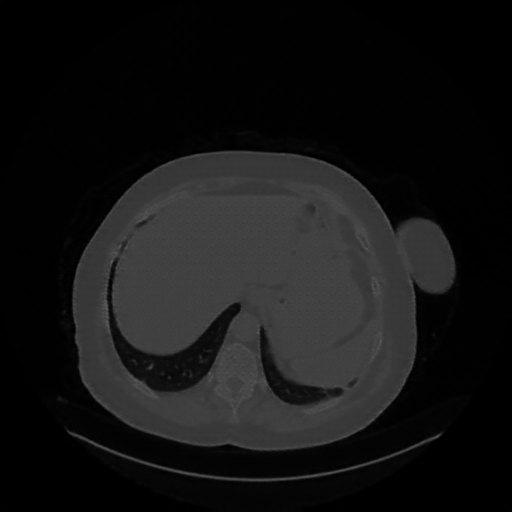

Generated VENOUS CT scan (A→B translation)

Full window (WL 1023.5, WW 4095 β†’ Low βˆ’1024, High +3071)

Lung window (WL -600, WW 1500 β†’ Low βˆ’1350, High +150)

Mediastinum window (WL 40, WW 400 β†’ Low βˆ’160, High +240)